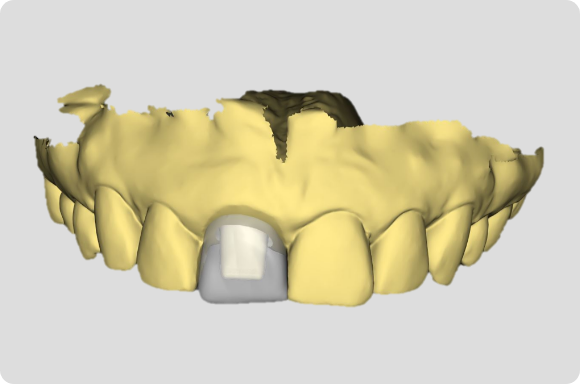

Utilizing procedure-based education1, this level will help the clinician grow into more advanced surgical and prosthetic concepts with the treatment of single tooth anterior implant cases

Throughout this level, the cases will cover topics including: Evaluating buccal and apical bone for immediate placement, Grafting around immediate implants (Dual Zone Technique), Defining implant orientation – The Rules of Six, Assessing primary stability for immediate provisionalization, CAD/CAM abutment options and designs. At the completion of this level, participants will understand how to place and restore a single-tooth implant in the anterior zone. Participants are encouraged to continue their education in Level 4, which will focus on multi-unit cases.